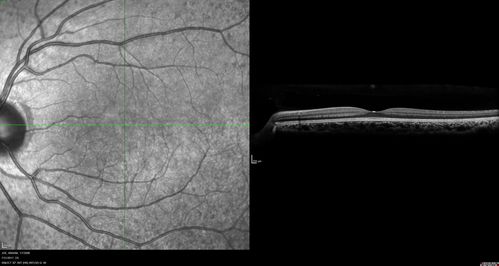

Fundus Albipunctatus

12 year old female with normal vision. She has 4 siblings all of whom have either white spots or spots on IR. Genetic testing by parents was deferred.